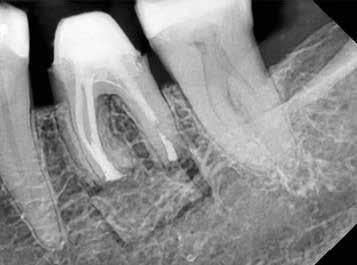

a kezdetleges kerámiavázat visszahelyezzük a csonkokra, a kerámia anyagában vékony repedések alakulnak ki. A végleges restaurátum elkészítéséhez szükséges kerámia „köpeny” ekkor áll készen a további kerámiarétegek felvitelére és kiégetésére (opaker réteg, dentin- és zománcmassza felvitele) (7-10. ábra). A készülő fogpótlás végső formai megjelenése rétegenként kerül kialakításra.

A második égetés során szintén csupán egy nagyon vékony réteg transzlucens opalmassza kerül felhelyezésre. A restaurátum formai megjelenésének és a felszíni textúrák kialakítására csak ezt követően kerül sor. A fényégetés során nem alkalmazunk glazúrmasszát. A készre vitel során elérni kívánt, magas fényű polírt kézi eszközök alkalmazásával alakítjuk ki. A restaurátumok végső kidolgozását követően a platinafóliát egy csipesz segítségével óvatosan eltávolítjuk, majd a kifejezetten vékony héjakat a kontroll mintára helyezzük. Ezt követően a pótlások megfelelő illeszkedésén kívül a funkcionális elmozdulások közben kialakuló érintkezéseket és a kontaktpontokat is ellenőrizzük. Az ilyenkor esetlegesen szükségessé váló korrekciók elvégzésére a Ducera® LFC (Dentsply Sirona) kerámiaanyagot használjuk. A kész munka fogorvosi rendelőbe való szállítása előtt kifejezett jelentőséggel bír az elkészült restaurátumok gondos becsomagolása. Az átadni kívánt fogpótlások sérülésmentes szállíthatóságának biztosítása elengedhetetlen az eddigi munkánk védelme szempontjából.

Rendelői fogpróba